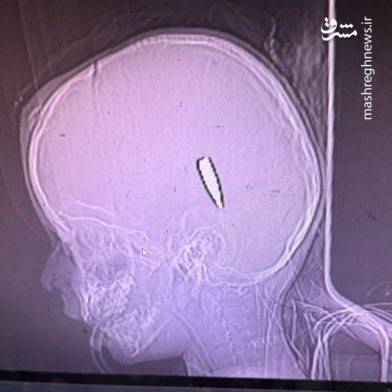

آنان با تصاویر رادیوگرافی از اعدام و شلیک به سر و گردن کودکان با (گلولههای ۵.۵۶ ناتو) مستندات آوردهاند و از کشتار، گرسنگی دادن و گورهای جمعی روایاتی هولناک کردهاند.